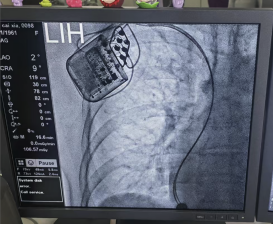

2025年9月12日,我院心内四科屈春红主任团队成功实施辽西地区首例心脏收缩力调节器(CCM)植入手术。此次创新治疗通过微创方式显著缓解了患者的心功能难题,为药物效果不佳、不适用再同步治疗的重度心衰患者提供了新的治疗选择,标志着医院在心衰治疗领域达到国内领先技术层次。

术中发现患者右房明显增大,下腔静脉增宽,三尖瓣重度返流,导致电极植入困难,在团队和导管室医技人员的密切配合下,先后植入两根主动起搏电极置于右室间隔。经过测试电极各项参数良好,CCM工作发送正常,患者各项生命体征平稳,手术全程仅40min左右。术后检查显示设备运行良好,患者生命体征平稳。